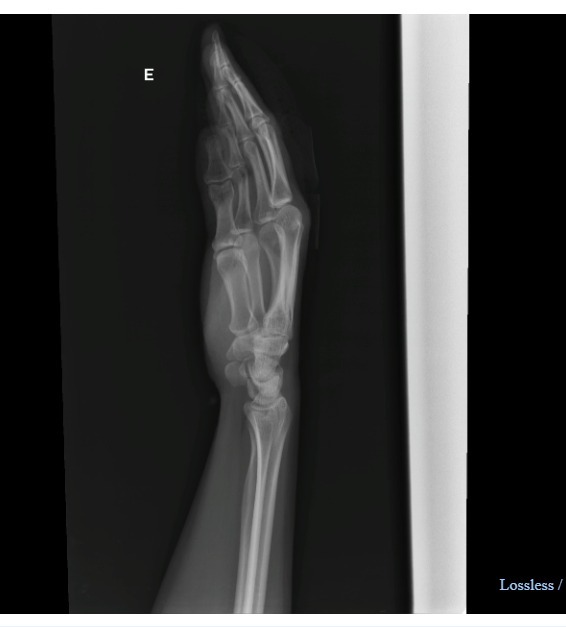

Moradora fratura a mão após acidente com patinete – Foto: Arquivo Pessoal/NDMoradora fratura a mão após acidente com patinete – Foto: Arquivo Pessoal/ND

Já Flora foi encaminhada para o Hospital Celso Ramos, em Florianópolis, onde foi diagnosticada uma fratura no dedo médio. “Levei 10 pontos e tive que tomar antibiótico e injeções, pois foi considerada fratura exposta”, alega.

Flora fraturou o dedo e precisou levar 10 pontos – Foto: Arquivo Pessoal/NDFlora fraturou o dedo e precisou levar 10 pontos – Foto: Arquivo Pessoal/ND